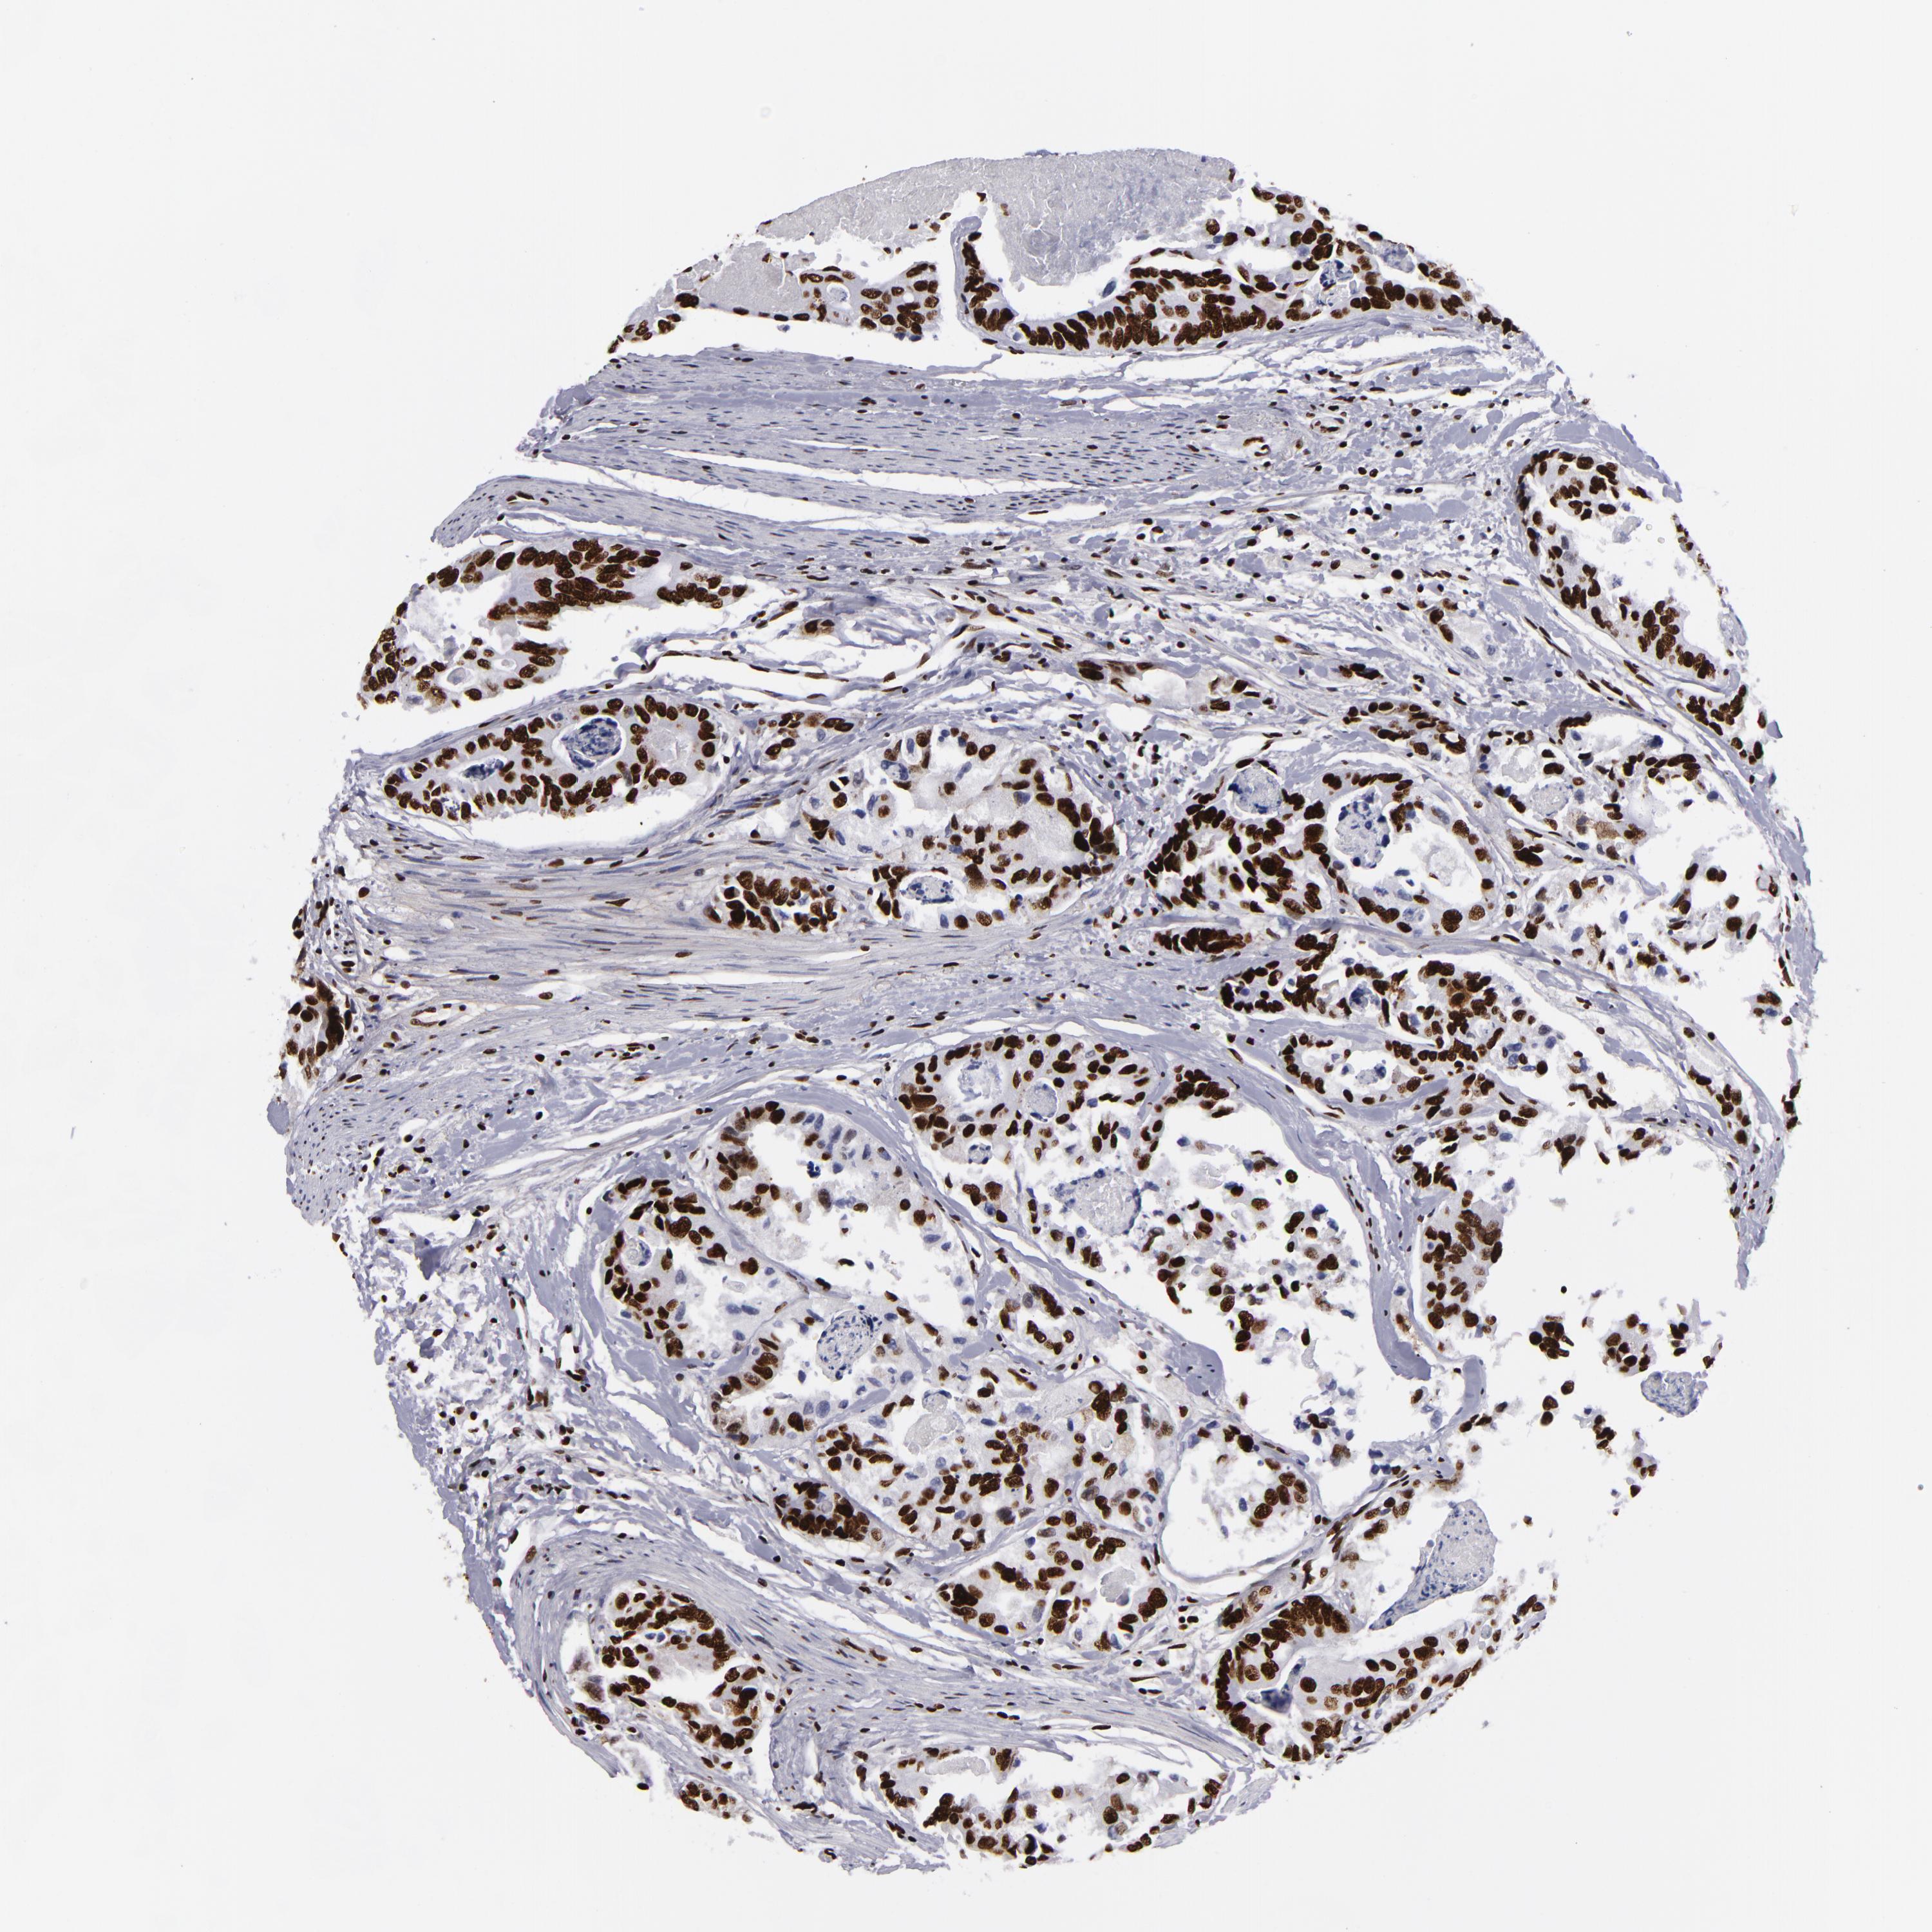

CANCER COLORECTAL CANCER Show tissue menu

Colorectal cancer

Human cancer

Colon adenocarcinoma